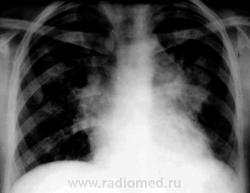

Пол пациента: Женский пол Тип патологии: Воспалительное заболевание неинфекционной природы Область исследования: Грудная клетка и верхние дыхательные пути Методы исследования: Rg Болеет около 3-х недель. Жалобы на одышку , сердцебиение. 10 дней принимала антибиотики. Возможно это сердечная патология? Бокового снимка нет. https://radiomed.ru/sites/default/files/styles/case_slider_image/public/user/12/1.Bod_..jpg?itok=E-KH1jBz https://radiomed.ru/sites/default/files/styles/case_slider_image/public/user/12/2.Bod_.jpg?itok=rzvtyFWz https://radiomed.ru/sites/default/files/styles/case_slider_image/public/user/12/3.Bod_..jpg?itok=2JC7feyE ID:1839 Втр, 16/03/2010 - 16:36 #1 tatyana Не на сайте Был на сайте: 4 года 1 месяц назад Зарегистрирован: 24.06.2009 - 08:33 Публикации: 2090 bogdan wrote: Возможно это сердечная патология? Вряд ли, скорее опухолевая "самоуверенность дилетантов - предмет зависти профессионалов" Втр, 16/03/2010 - 18:29 #2 ElenaG Не на сайте Был на сайте: 15 лет 7 месяцев назад Зарегистрирован: 23.02.2010 - 23:21 Публикации: 69 Хотелось бы узнать возраст пациентки.ятоже за онкологию,Хотя и правый корень кажется расширен.Не окажется ли это лимфоузлами? Втр, 16/03/2010 - 18:30 #3 Лукаш Не на сайте Был на сайте: 10 лет 3 месяцев назад Зарегистрирован: 05.03.2010 - 13:28 Публикации: 47 А может быть и саркоидоз или ЛГМ (возраст какой?). Есть признаки сдавления верхней полой вены? Ой, больной, что-то мне ваш снимок не нравится. Но ничего - щас мы в Фотошопе все подправим. Втр, 16/03/2010 - 20:19 #4 bogdan Не на сайте Был на сайте: 7 лет 1 месяц назад Зарегистрирован: 07.01.2010 - 16:14 Публикации: 45 Девушке 23 года Втр, 16/03/2010 - 21:04 #5 Петрович Не на сайте Был на сайте: 7 лет 2 месяцев назад Зарегистрирован: 22.03.2009 - 01:13 Публикации: 3908 А почему не сделана хотя бы левая боковая проекция? Болеет давно, клиника серьёзная. Пора уже и томограммы делать. Вон как средостение расширено. Неоднозначно всё Втр, 16/03/2010 - 23:53 #6 Лукаш Не на сайте Был на сайте: 10 лет 3 месяцев назад Зарегистрирован: 05.03.2010 - 13:28 Публикации: 47 Возраст молодой - надо исключать лимфогранулематоз: поискать периферические лимфоузлы, при нахождении - пропунктировать. Еще УЗИ ОБП - на предмет парааортальных л/у. Ой, больной, что-то мне ваш снимок не нравится. Но ничего - щас мы в Фотошопе все подправим.

А почему не сделана хотя бы левая боковая проекция? Болеет давно, клиника серьёзная. Пора уже и томограммы делать. Вон как средостение расширено.

Неоднозначно всё